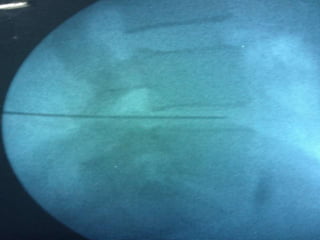

 Material and methods:

 Percutaneous ablating techniques of intervertebral disc are performed

under fluoroscopy guidance with patients in prone position for lumbar

discectomy.

 Intervertebral disc of interest was squared in antero-positerior

projection. Scotty Dog projection was attained in oblique view.

 Needle advancement was performed under fluoroscopic control with AP

and Lateral views.

 Annulus fibrosus puncture can be both felt as well as seen under

fluoroscopy.

 Working distance of disc was determined and needle guard was placed

accordingly.

 Stylet was removed and Stryker decompressor was placed in a needle

and properly locked.

 The decompressor was switched on and needle and decompressor

were moved as a single unit over a distance of one centimeter or as

directed by C-arm picture and about 1-1.5ml of gelatinous nucleus

pulposus was removed.

.  Material andmethods:  Percutaneous ablating techniques of intervertebral disc are performed under fluoroscopy guidance with patients in prone position for lumbar discectomy.  Pre-procedural antibiotic (Amoxiclav 1.2gm) was given 45 minutes prior to the procedure.  Under all aseptic precautions, standard ASA monitored attached , iv line secured with 20 gauge iv cannula and iv fluid started @ 100ml/hr  Conscious sedation was attained with intravenous midazolam 1mg and IV fentanyl 1mcg/ Kg and repeated if required.  Intervertebral disc of interest was squared in antero-positerior projection. Scotty Dog projection was attained in oblique view.  Percutaneous Needle was placed under local anesthesia under C-arm guidance with Utmost care to avoid nerve roots contact and whenever patient complain of pain radiating to legs the direction of needle was changed.  Needle advancement was performed under fluoroscopic control with AP and Lateral views.

 Annulus fibrosuspuncture can be both felt as well as seen under fluoroscopy.  Working distance of disc was determined and needle guard was placed accordingly.  Stylet was removed and Stryker decompressor was placed in a needle and properly locked.  The decompressor was switched on and needle and decompressor were moved as a single unit over a distance of one centimeter or as directed by C-arm picture and about 1-1.5ml of gelatinous nucleus pulposus was removed.  After completion of procedure 1ml of injection Acuclav was given in the disc space.  Assembly was removed and aseptic dressing was applied.  The patient was asked to move his lower limb to check any injury to nerves by comparing with other side.  Patient kept in recovery for 3 hrs and sent home if fit with clear instructions to accompanying person.